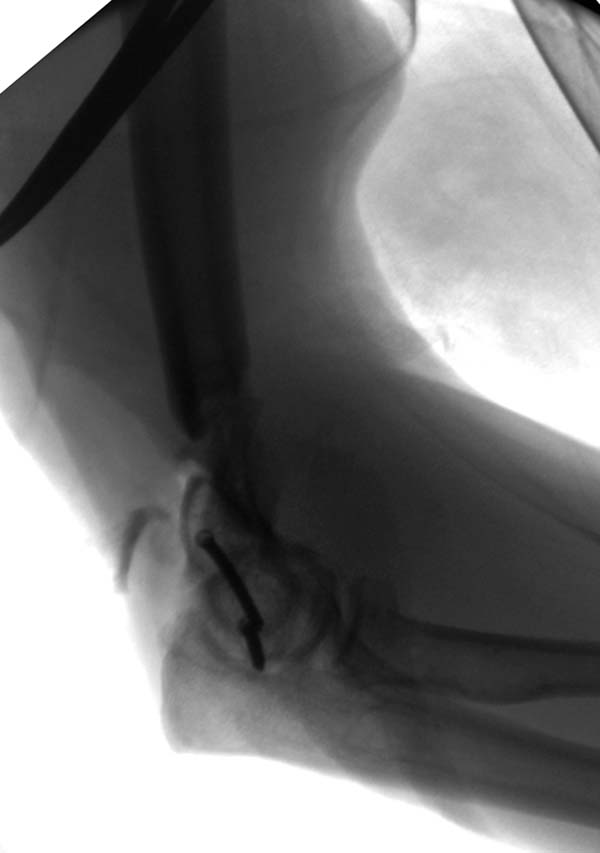

Примеры: первому более 15 лет фиксирован шурупом и tension band technique, а второй перелом открытый больной 80 лет, после наружного фиксатора в первом этапе и окончательная фиксация вторично. Третьий раз внесуставная остеотомия...

Прошу прощения за неполный ответ. Еще раз: Спасибо Джолдас за великолепную презентацию. В третьем случае, если я правильно понял, Вы сперва выполнили закрытую репозицию и чрескожную фиксацию отломков под контролем С-дуги. И затем перешли к открытому этапу, не так ли? Чем Вы руководствовались в выборе такой тактики?